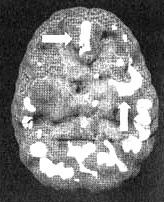

Полученные результаты были далеко не нормальны. Активность префронтальной коры оставалась нормальной в состоянии покоя, но снижалась, когда Пол пытался сосредоточиться (свидетельствует об импульсивности). В глубоких тканях левой височной доли была выявлена выраженная повышенная активность (вспыльчивость). Повышенная активность была обнаружена и в поясной извилине (фиксация на мыслях).

Мозг Пола. Агрессивность

Трехмерное изображение снизу — активный мозг.

Трехмерное изображение сбоку — активный мозг.

Обратите внимание на выраженно повышенную активность в левой височной доле и в поясной системе (стрелки).